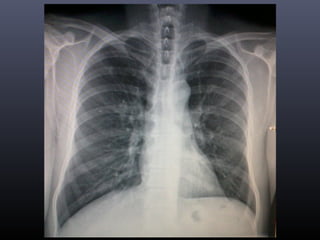

• En radiografía de tórax se evidencia nódulo pulmonar izquierdo.

• Se envía para certificación.